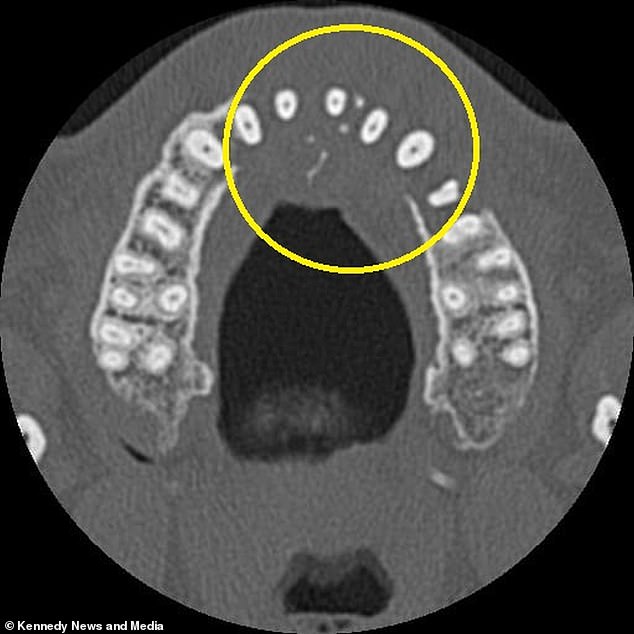

The turning point came during a routine dental visit in Portugal, which Mr. Vieira chose partly due to the lower cost of care compared to the UK. A standard X-ray at the clinic revealed an alarming absence of bone on the left side of his upper jaw. This discovery prompted further imaging, including a CT scan, which exposed a mass invading his sinus cavity and spreading toward his nose. These findings led to a referral back to the UK for specialized testing, where doctors confirmed a stage two diagnosis of diffuse large B-cell lymphoma (DLBCL), a particularly aggressive subtype of non-Hodgkin lymphoma that targets white blood cells. The tumour had already eroded his upper jawbone and begun metastasizing to his neck, a progression that underscores the rapidity of this disease.